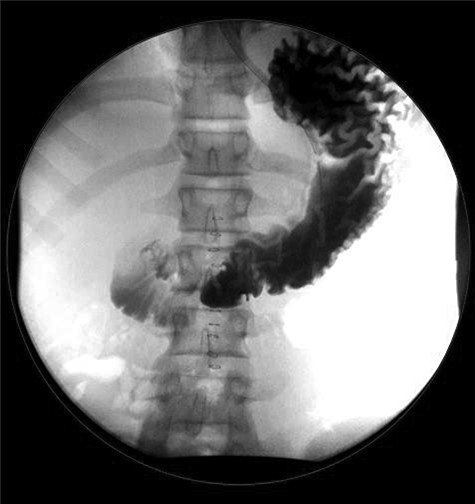

Case 2: A 13-year-old girl presented to the ED with a 3-day history of severe diffuse intermittent abdominal pain, worse in the periumbilical area, associated with nausea, vomiting and non-bloody diarrhea. No significant history was reported. On exam, the patient appeared sick, in acute distress, tachycardic and tachypneic with abdominal exam revealing diffuse tenderness with peritoneal signs. Laboratories showed normal WBC but lactic acidosis. Chest X-ray did not show free air under diaphragm (Fig. 3) and abdominal ultrasound showed moderate fluid in right upper quadrant of abdomen, for which CT of the abdomen and pelvis was ordered and it revealed free mesenteric fluid and extraluminal air in the pelvis suspicious for hollow viscus perforation (Fig. 4).

Diffuse infiltration of the mesentery is seen. A component of bowel wall thickening is seen in the distal ileum and the transverse colon. In the pelvis, a focus of extraluminal air is seen on the right. Free mesenteric fluid is seen as well.